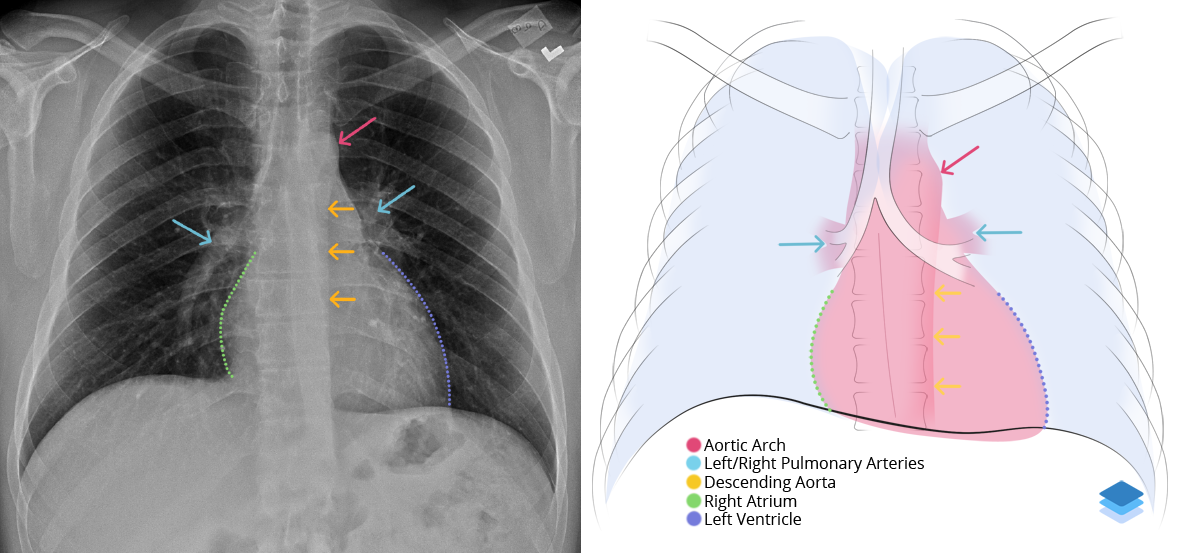

Age: 77

Sex: Female

Indication: Fever

Sample ReportAscending aortic aneurysm. Recommend chest CTA for further evaluation.

Otherwise, no evidence of acute cardiopulmonary disease.